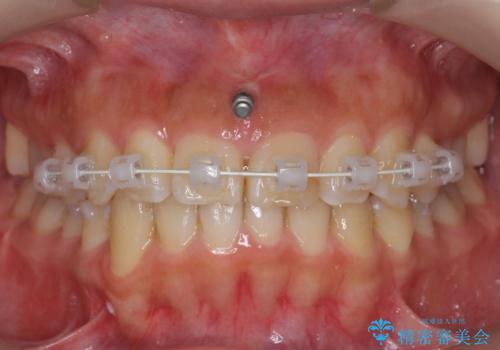

前歯のがたつき ガミースマイルの改善

- 前歯のがたつきとガミースマイルの改善を希望して来院。

ガミーは非常に軽度でひどくはなかったのですが、改善を強く希望されていました。

上の前歯をひっぱりあげて目立たなくするために、上の前歯のワイヤー部分矯正を行い、ミニスクリューからわずかに引っ張り上げました。

また、右上の犬歯の反対咬合についてもワイヤー矯正で短期間で改善することができました。

前歯の過蓋咬合についても改善しています。